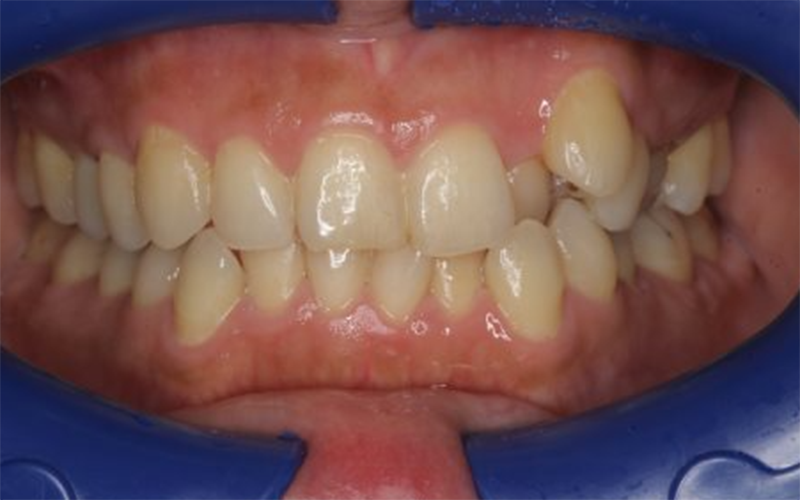

叢生および咬合不正に対して矯正治療を行った症例(20代女性)

歯並びのガタつきと前歯の噛み合わせが気になるとのことで来院されました。特に前歯の重なりや歯列の乱れを改善したいとのご希望でした。 |

上下顎前歯部に叢生が認められ、歯列全体のバランスが崩れている状態でした。前歯の重なりにより審美性だけでなく清掃性の低下も懸念される状態でした。 |

歯列全体のバランスを整えるため、矯正治療による歯列改善をご提案しました。歯の配列を整えながら咬合関係を改善し、審美性と機能性の両立を目指して治療を進めました。 |

歯列の重なりは改善し、前歯の見た目が整いました。咬合バランスも改善し、全体的に自然で調和の取れた歯並びとなりました。ただし患者様が海外移住予定となったため、当院での治療は途中段階で終了となりました。 |